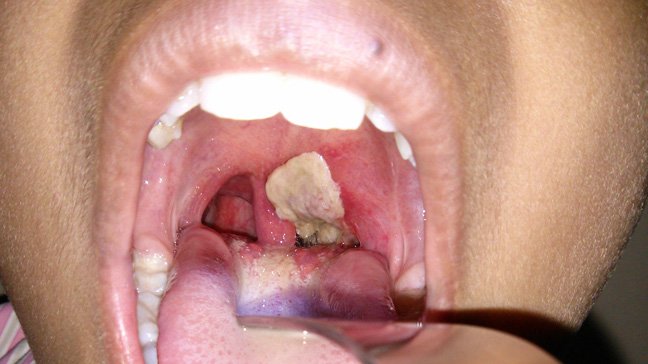

Diphtheria, caused by a toxin produced by the bacteria Corynebacterium diphtheriae, is a vaccine-preventable disease covered by one of the vaccines provided routinely through Nigeria’s childhood immunization schedule.